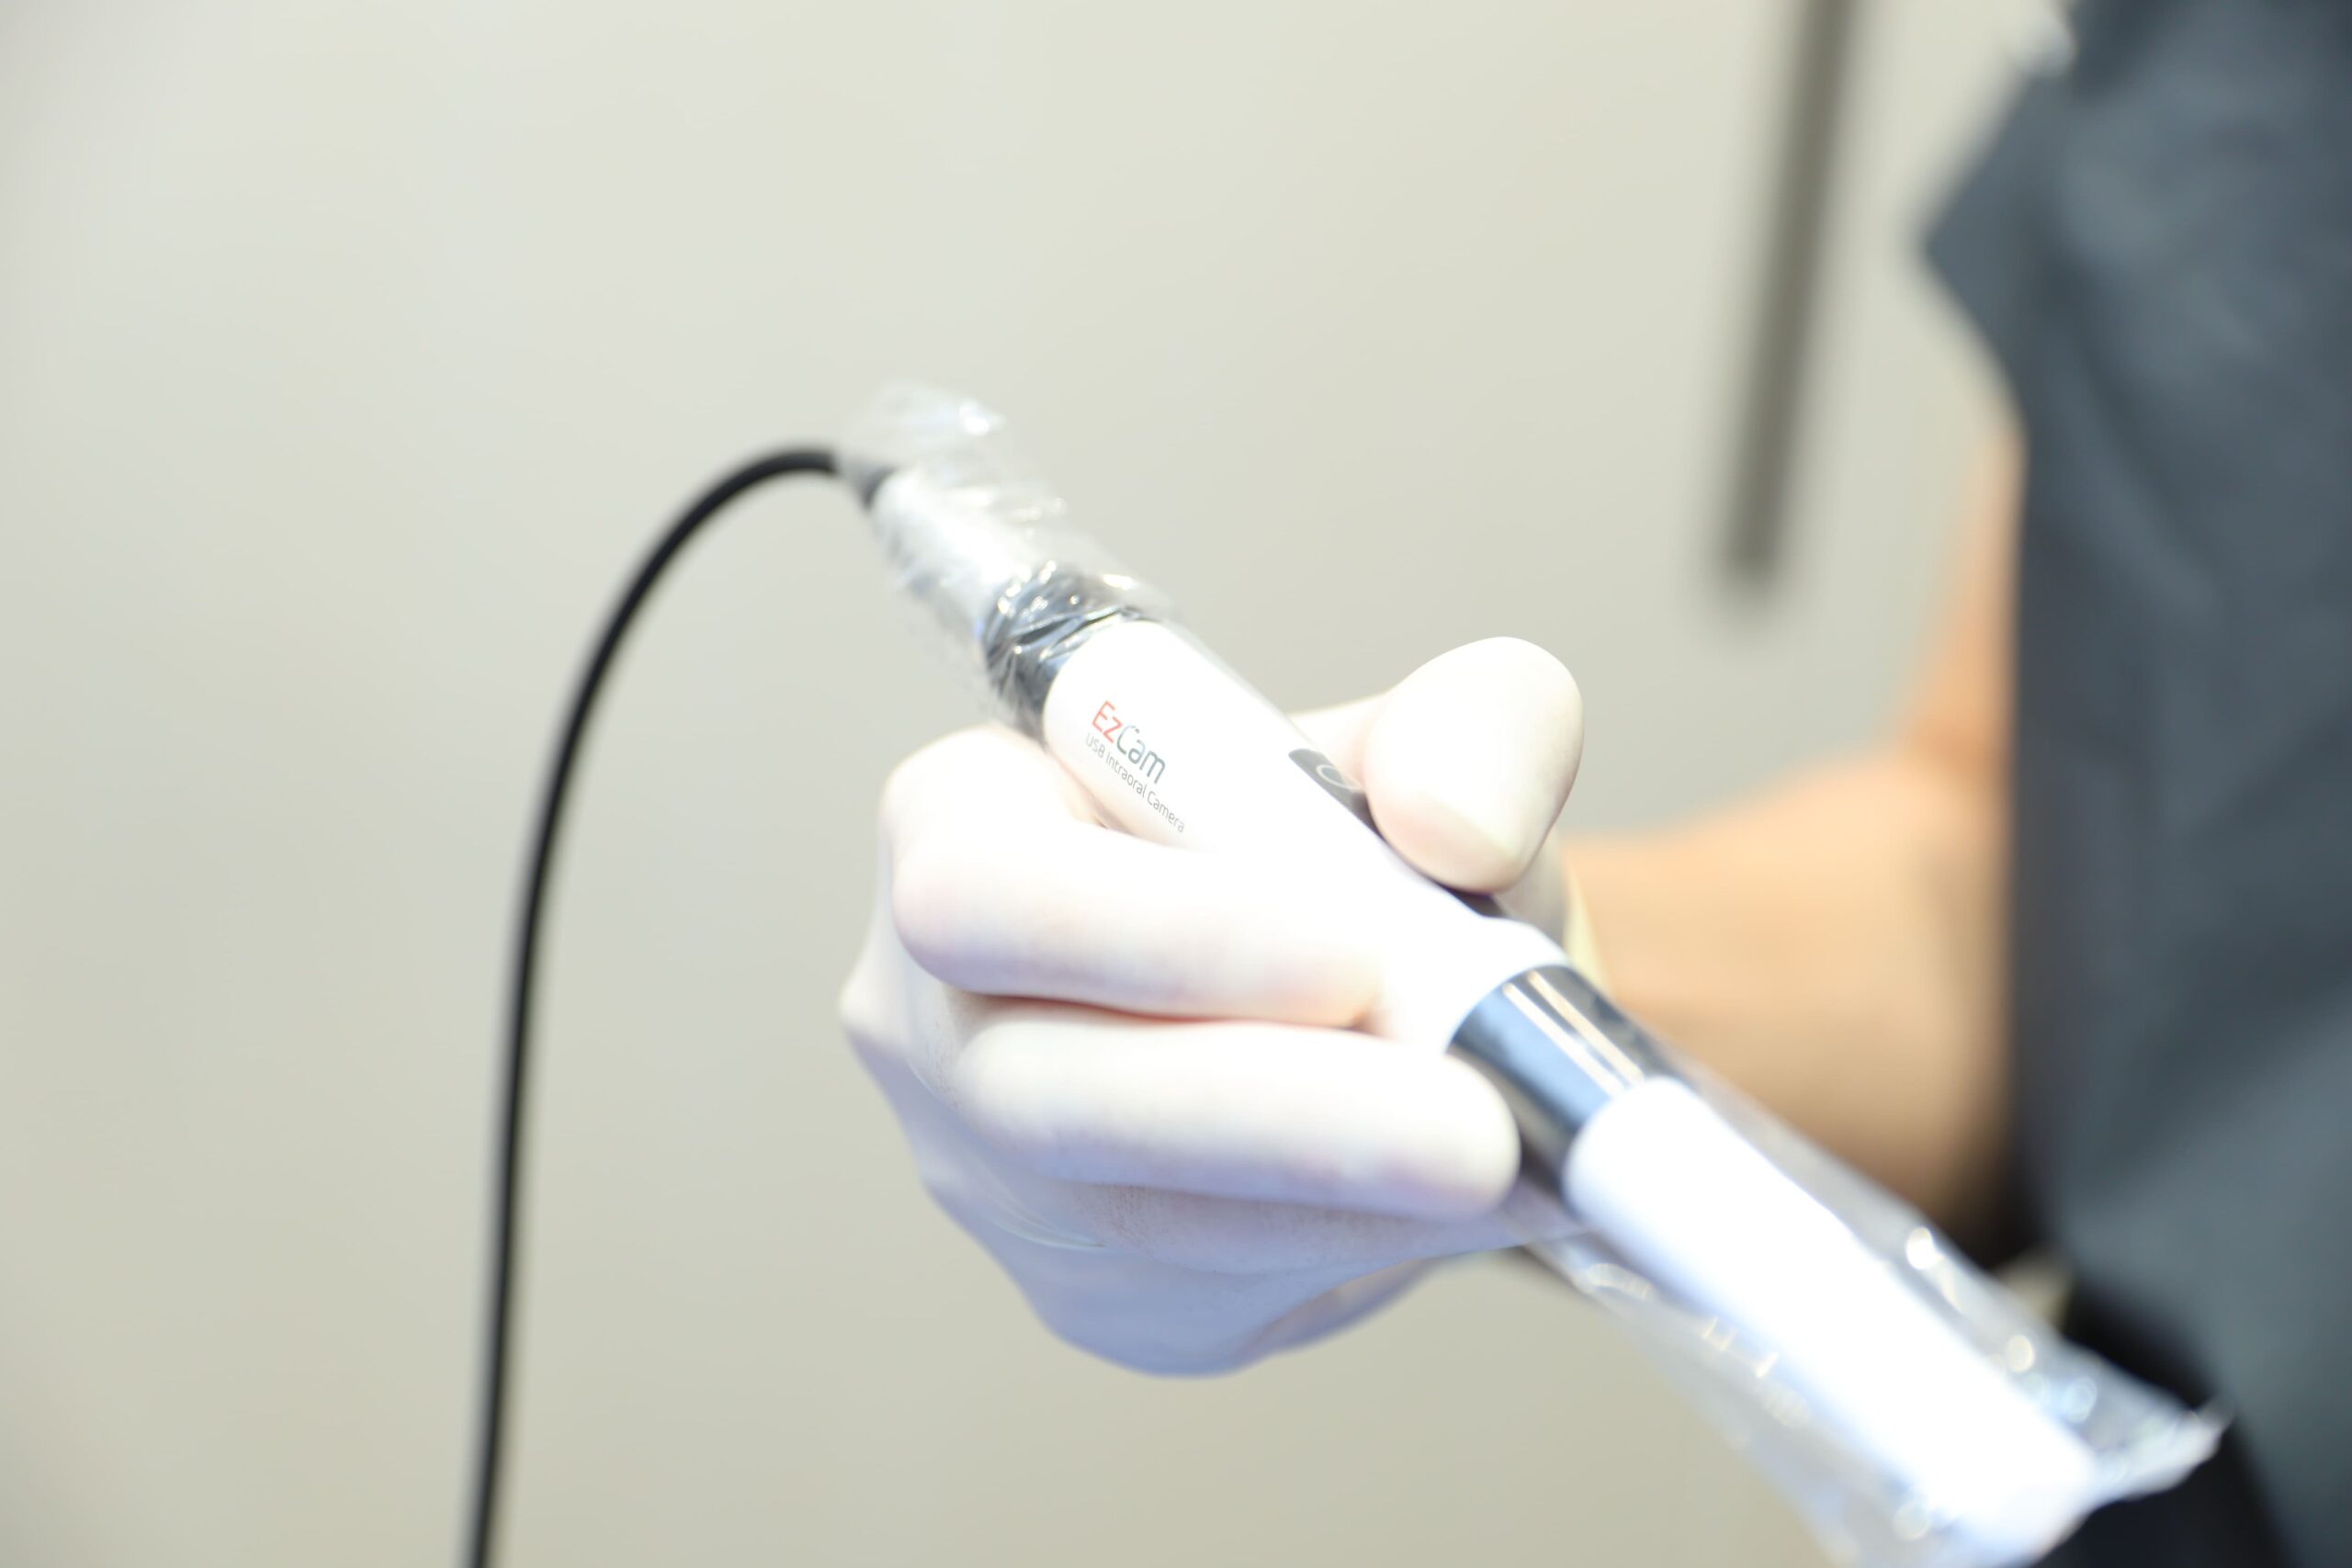

口腔内スキャナーによるむし歯の検知

当院が導入する口腔内スキャナーは、患者様の歯を非侵襲的にスキャンし、内部の状態を視覚化します。これは、放射線を使用せず、近赤外光画像技術によって歯の内部のむし歯や隣接面のむし歯を発見することが可能です。さらに、内蔵の口腔内カメラで撮影したカラー画像をリアルタイムでモニターに映し出し、患者様自身もその場で確認できるため、治療や予防に対する理解を深める助けとなります。